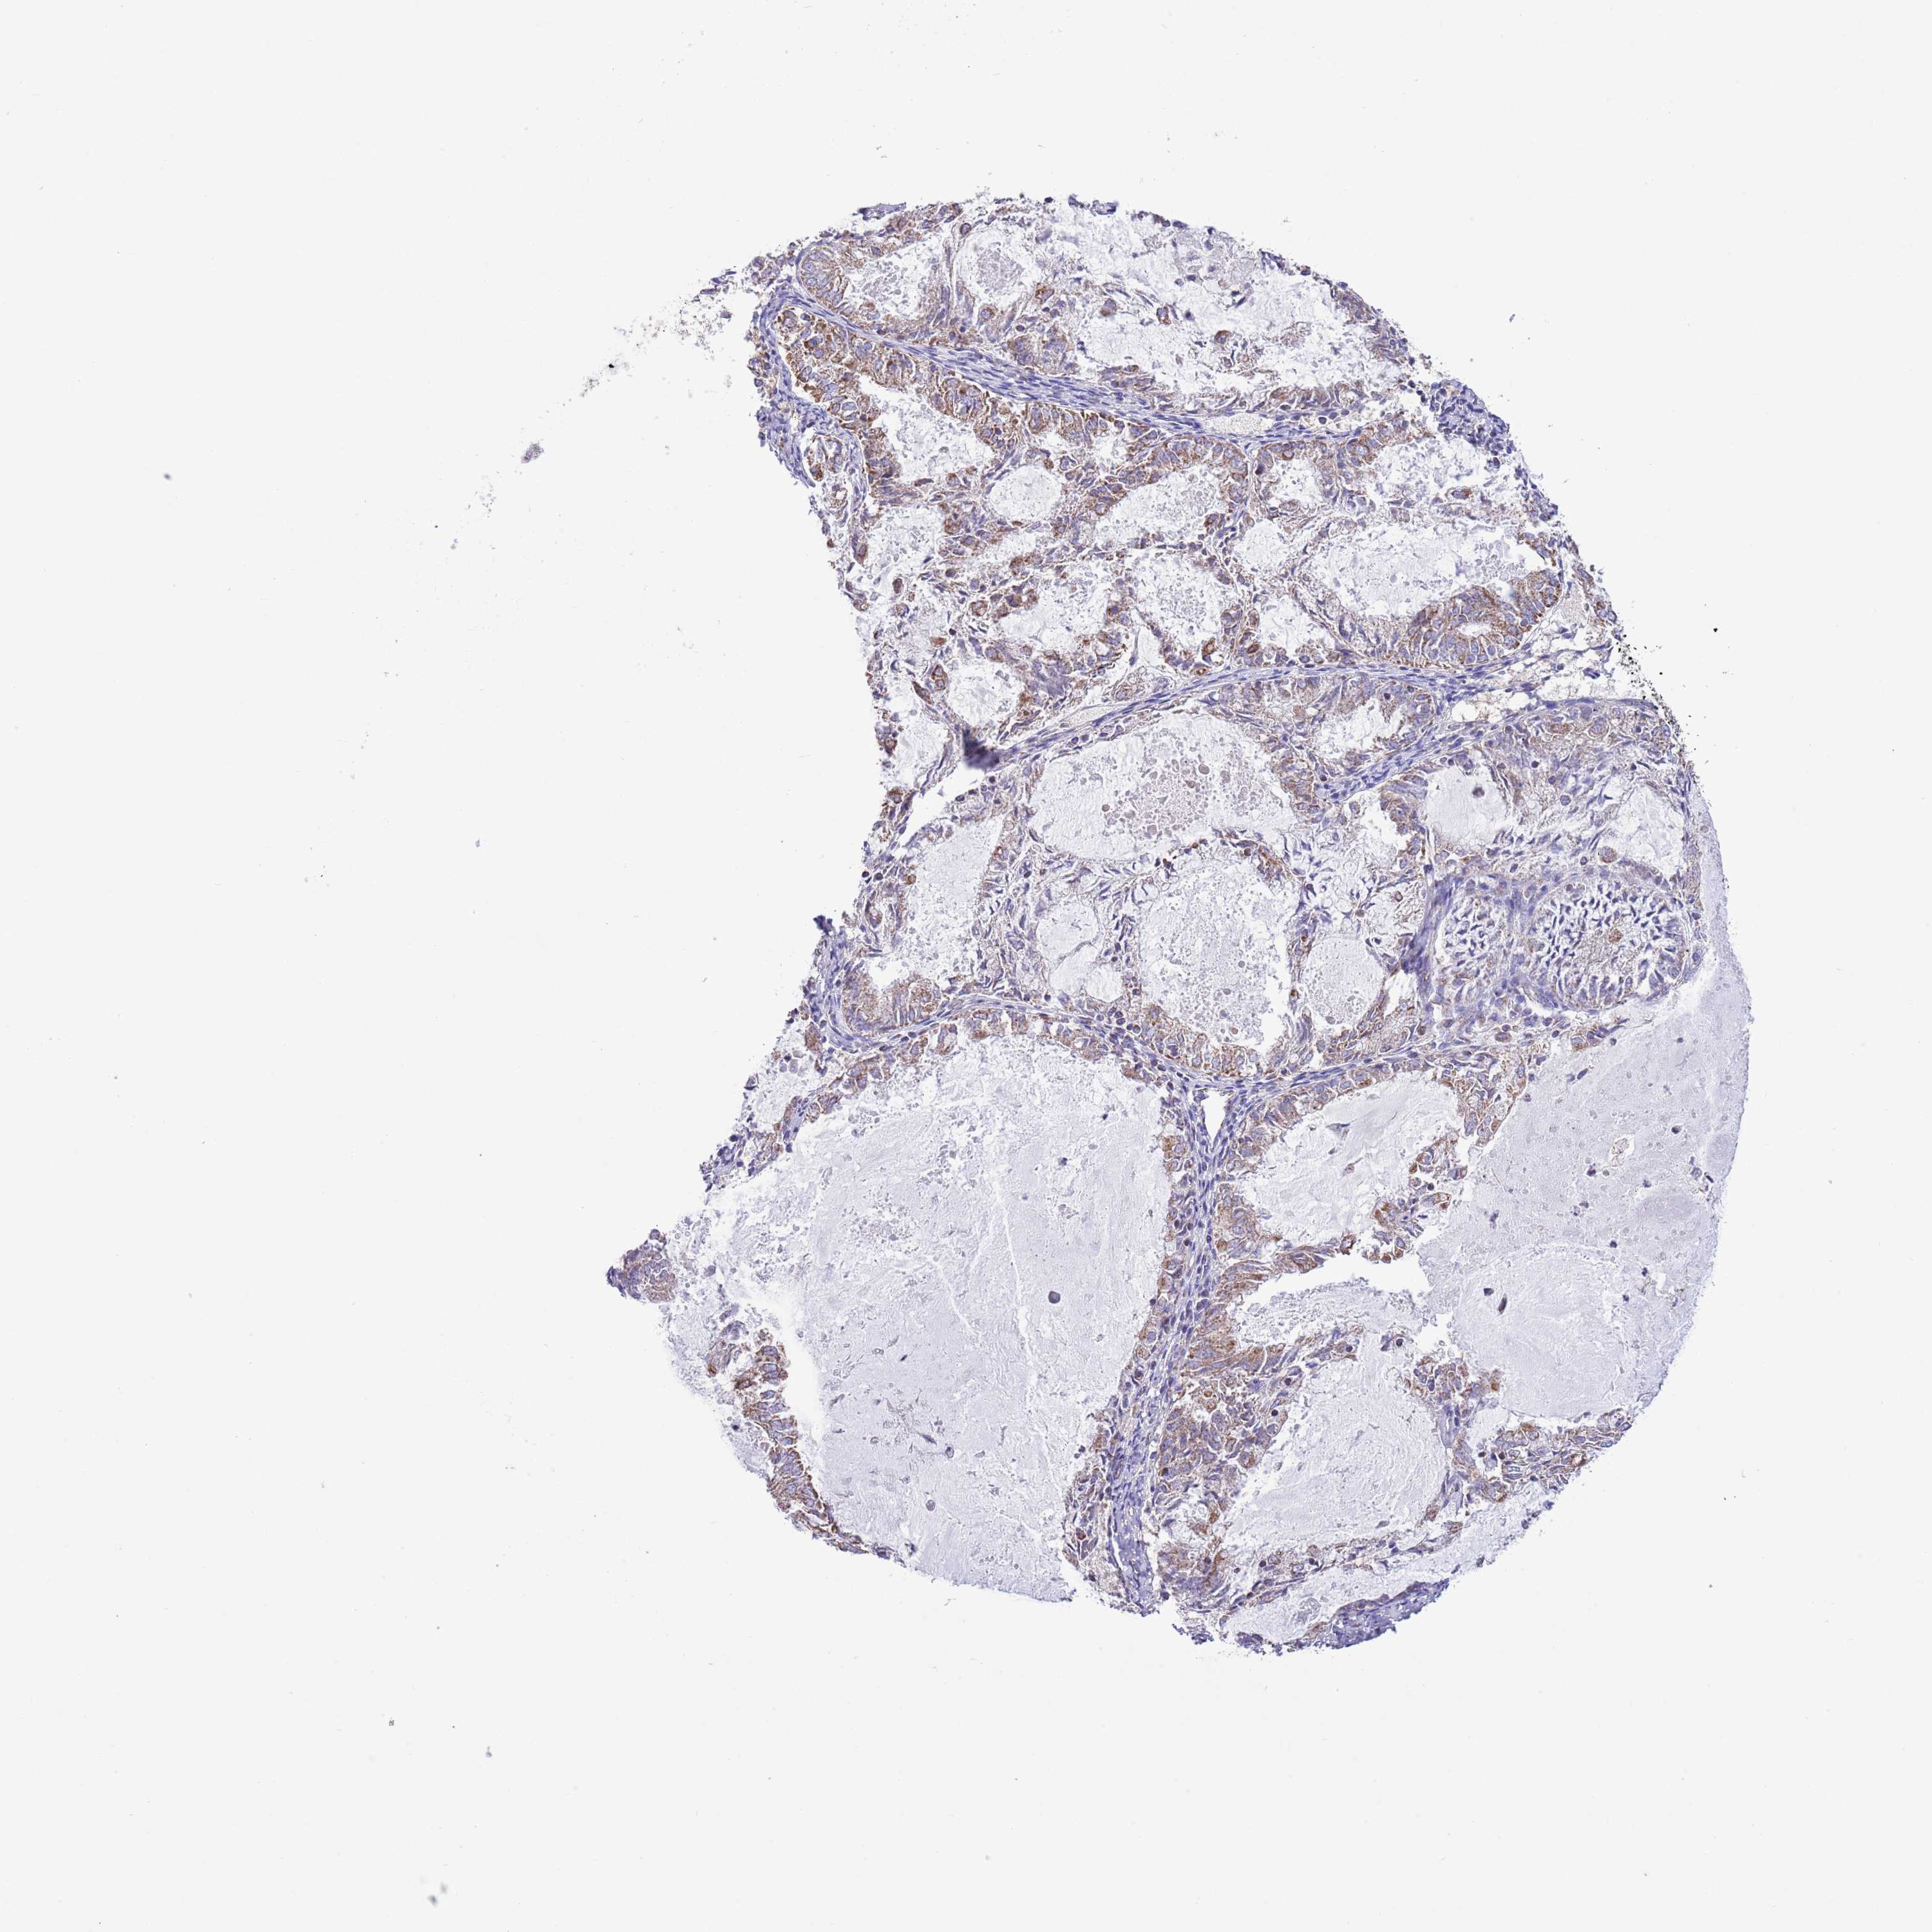

ENDOMETRIAL CANCER - Protein expressioni

A mouse-over function shows sample information and annotation data. Click on an image to view it in a full screen mode. Samples can be filtered based on level of antibody staining by selecting one or several of the following categories: high, medium, low and not detected. The assay and annotation is described here.

Note that samples used for immunohistochemistry by the Human Protein Atlas do not correspond to samples in the TCGA dataset.

Antibody stainingi

Antibody staining in the annotated cell types in the current human tissue is reported as not detected, low, medium, or high, based on conventional immunohistochemistry profiling in selected tissues. This score is based on the combination of the staining intensity and fraction of stained cells.

Each image is clickable and will lead to virtual microscopy that enables deeper exploration of all samples and also displays staining intensity scores, fraction scores and subcellular localization as well as patient and tissue information for each sample.

Antibody HPA048654

Staining

High

Medium

Low

Not detected

Intensity

Strong

Moderate

Weak

Negative

Quantity

>75%

75%-25%

<25%

None

Location

Nuclear

Cytoplasmic/membranous

Cytoplasmic/membranous,nuclear

Adenocarcinoma, NOS